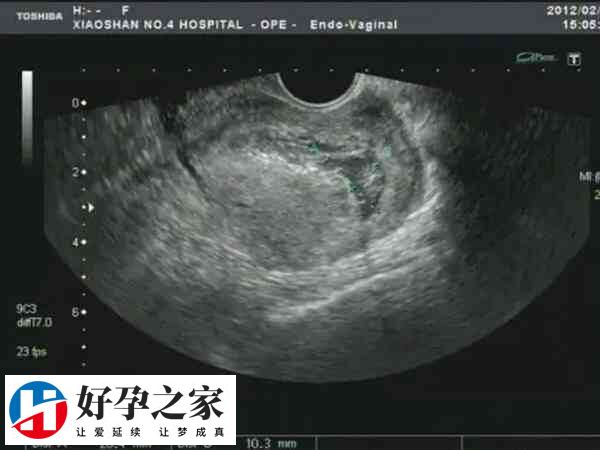

移植囊胚并不一定能成功。囊胚通常是指发育到第5天或第6天的胚胎,是胚胎在体外发育的终末阶段。由于培养...

做试管婴儿,取卵当天为Day0。精子和卵子受精后,在体外培养会经过以下不同的时期,取卵后第1天(Da...